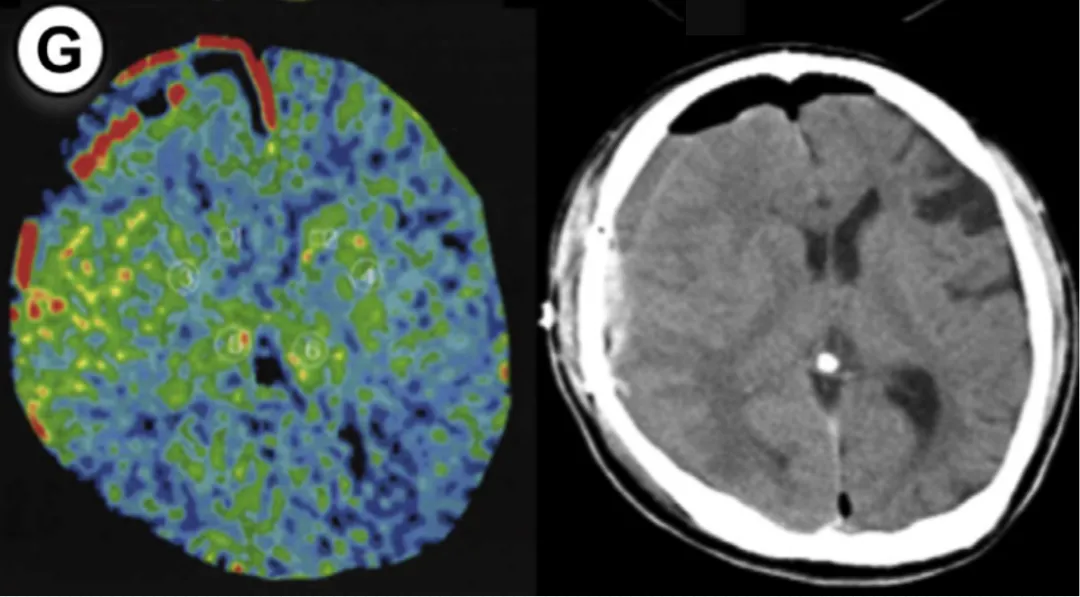

55岁男性,因颅内出血确诊烟雾病,行右侧大脑手术。方法1显示rCBF增加率47%,方法2为55%(超过50%阈值)。术后第3天中断镇静,第2天发生脑出血,改良Rankin量表评分恶化。

49岁女性,有TIA病史,行右侧大脑手术。方法1 rCBF增加率89%,方法2达133%。术后即时CT无异常,但第5天发现硬膜下血肿合并蛛网膜下腔出血。